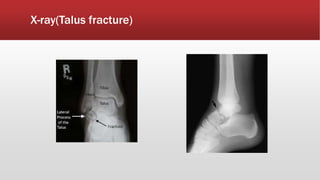

X-ray(Talus fracture)

Talus fracture

▪ Talus fracture is an injury of the hind

foot

▪ Rare, occur due to considerable

violence with axial loading or hyper

dorsiflexion.

▪ Injuries include fracture of the head,

neck, body, or bony processes of

talus.

▪ Patients present with painful and

swollen foot and ankle

▪ Obvious deformity if fracture is

displaced

▪ Skin overlaying the fracture or

dislocation may be tented or split